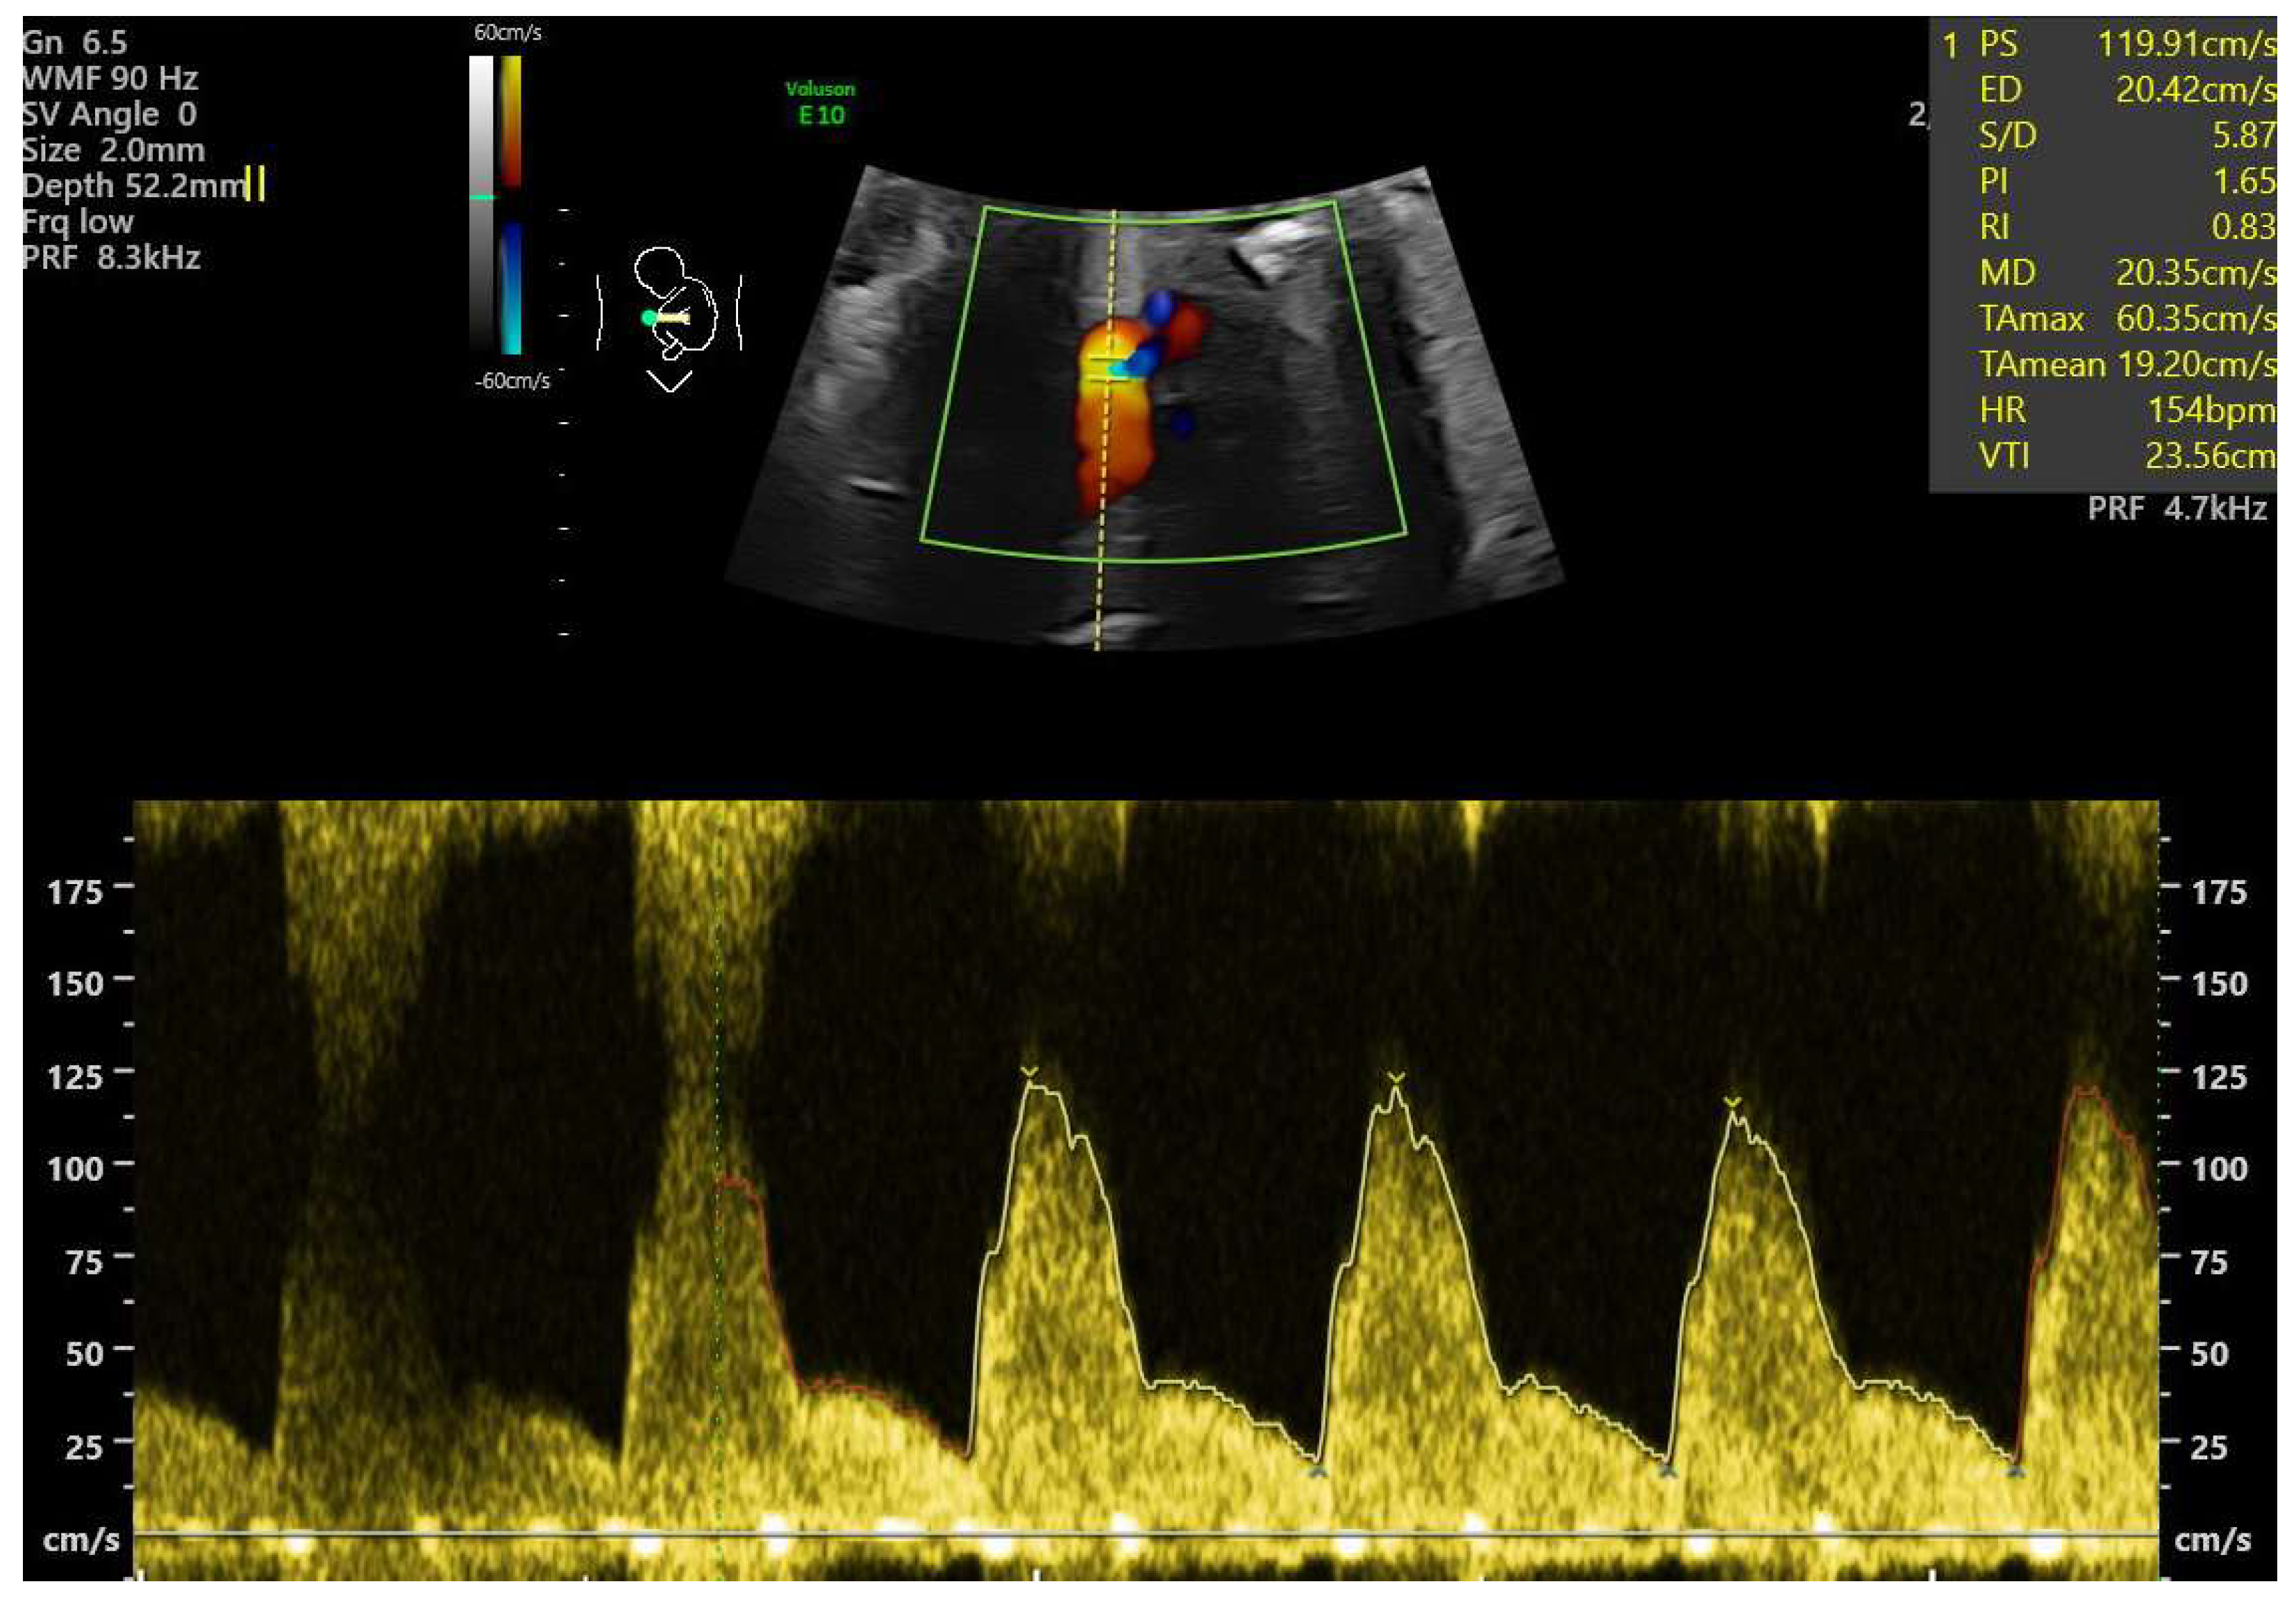

- Ductal constriction (DC), defined as a peak systolic velocity (PSV) > 1.4 m/s or >95th percentile for gestational age, a peak diastolic velocity > 35 cm/s or >95th percentile, or a pulsatility index (PI) < 1.9 [8,9]. The measurement was taken by visualizing the DA at the 12th or 6th “hour” (+/− 30 degrees), which was performed by seeing the ductal arch in the long-axis view. Fetal slow movements or hiccups were accounted for and if they occurred the measurement was taken more times during the examination (Figure 2).